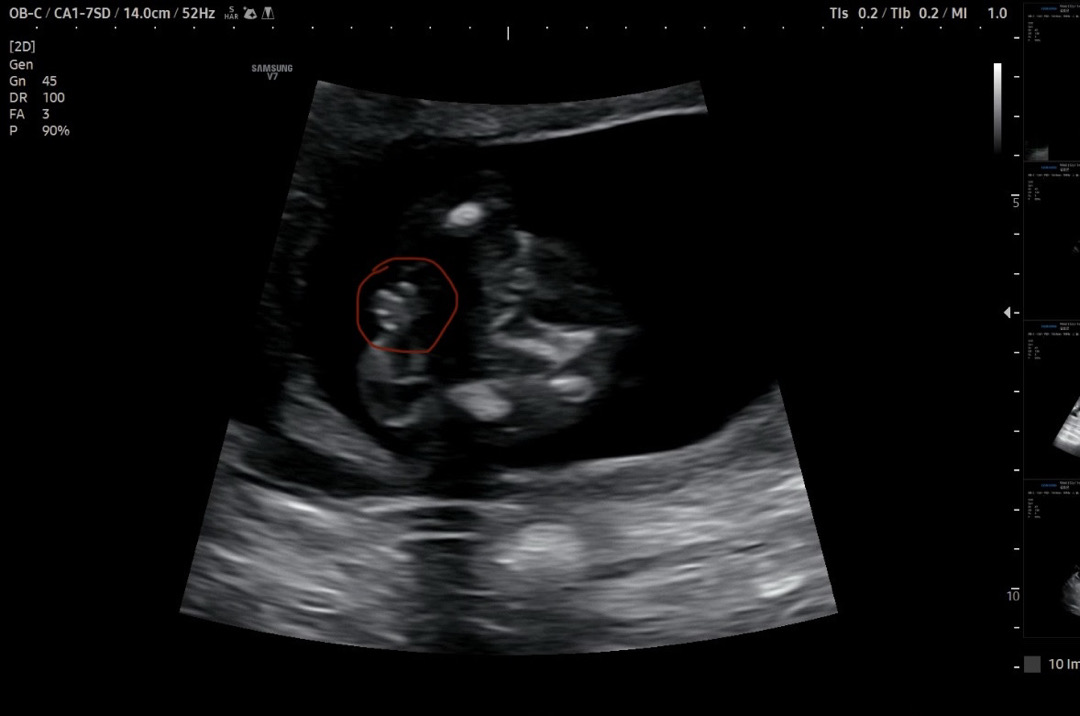

탯줄같나요 🌶️같나요ㅠㅠㅠ?

제가 이런글을 올릴줄이야 ㅋㅋㅋㅋ 한달만에 가서 2차기형아 하는김에 성별 여쭤보니.. 애매하다는 답변을 받았어요ㅠㅡㅠㅋㅋㅋㅋ 탯줄 같은데.. 라고하시면서 이게 고환이고 이게 🌶️같아보이긴해요 라고만 하시네요 ㅠㅠㅠㅠ 70퍼 확률로 아들같다 라고 하시는데 보기에 어떠신가용?ㅋㅋㅋ 벌써 16주 6일차라... 저게 탯줄이 아니면 아들확정이라능건뎅...! 뭔가 그 주위에 메추리알(?)처럼도 보이는거 같아서 진짜 애매하네요 ㅠㅠㅠ 영상이 안올라가서 아쉽 ㅠㅠㅠㅠ